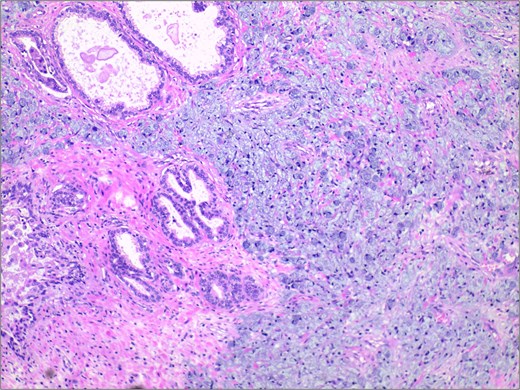

In November 2024, the patient presented with progressive dysuria for 3 years, accompanied by recurrent urinary retention for 3 weeks. Physical examination revealed a prostate enlarged to grade II, with a firm texture, smooth surface, no palpable nodules, no tenderness, a shallow median sulcus, and no sphincter relaxation. Imaging studies with 3.0 T prostate magnetic resonance imaging (MRI) showed a prostate measuring ⁓5.7 × 4.8 × 5.7 cm, with marked enlargement of the transition zone and heterogeneous signals. Small, patchy short T2 signals were internally observed, along with slightly high diffusion-weighted imaging (DWI) signals and slightly decreased apparent diffusion coefficient (ADC) signals, yielding a PI-RADS score of 3. The peripheral zone was thinned and indistinct. The seminal vesicles showed normal size and morphology, and the bladder-seminal vesicle triangle was intact. No enlarged lymph nodes were evident in the pelvic cavity. Laboratory tests showed a total prostate-specific antigen level of 1.759 ng/ml. Initially diagnosed with benign prostatic hyperplasia, the patient underwent transurethral enucleation of the prostate with a thulium laser under general anesthesia on 19 November 2024. The surgery was successful. Postoperative pathology indicated poorly differentiated adenocarcinoma, predominantly signet ring cell carcinoma, presumed to be of gastric origin (Fig. 1). Immunohistochemical analysis revealed negativity for prostate cancer markers (PSA and P504S) and positivity for gastrointestinal tumor markers [CKP(3+), CK20(+), CEA(3+), Villin(2+), CDX-2(2+)] (Fig. 2). Morphological comparison with previous gastric cancer pathology slides showed similar features, confirming metastatic gastric signet ring cell carcinoma to the prostate. The patient continued chemotherapy with the original gastric cancer regimen postoperatively and is currently under follow-up.

Histopathological examination revealed extensive infiltration of signet-ring cells, with the cytoplasm filled with mucinous vacuoles, and the nuclei showing eccentric positioning and dark staining. H&E stain 40×.